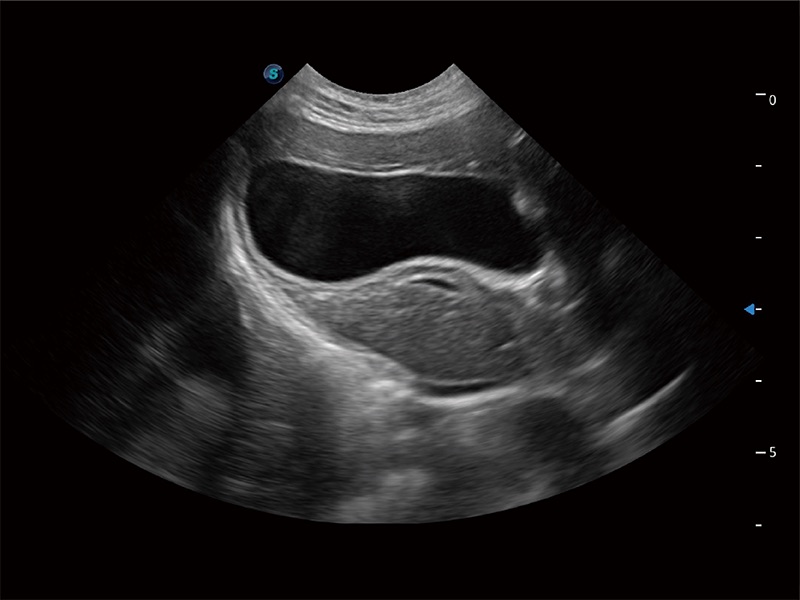

高性能和先进的临床应用工具可以为动物医生提供临床信心。ProPet 80 搭载了先进的腹部和浅表应用工具,帮助医生在日常临床实践中发挥前所未有的作用。

ProPet 80 配备了丰富的心脏探头群、先进的成像技术和专业的心脏测量工具,可帮助动物医生为不同体型和生理结构的动物提供心脏和心肌功能的全面评估。

ProPet 80 专为动物医生设计,对不同的动物体型和生理结构作出了针对性的优化。通过动物影像专用软件,可满足个性化的应用需求,帮助动物医生获得更精确的诊断数据。

ProPet 80 全新的动物超声智能软件和丰富的探头群,为动物医生提供了高清晰度和精细分辨率的图像,无论在宠物、马科、畜牧还是实验室动物等应用中都可以轻松应对,为您的日常工作带来满意的体验。